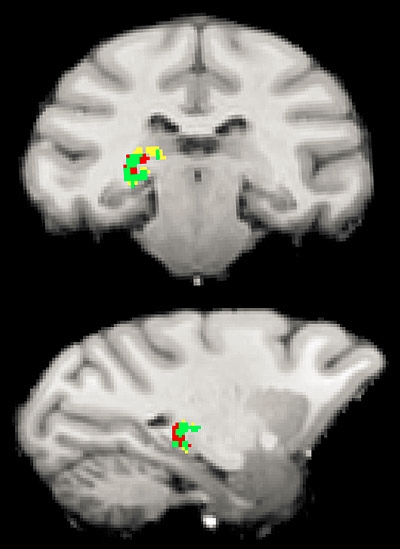

5772.06.01, 1200 Princeton study (EurekAlert): "A mysterious region [the pulvinar] deep in the human brain could be where we sort through the onslaught of stimuli from the outside world and focus on the information most important to our behavior and survival, Princeton University researchers have found. … the pulvinar regulates communication between clusters of brain cells as our brain focuses on the people and objects that need our attention. Like a switchboard operator, the pulvinar makes sure that separate areas of the visual cortex — which processes visual information — are communicating about the same external information"

| "After producing neural connection maps, the researchers used electrodes (blue arrows and green crosshairs) to monitor the direct communication paths (yellow-orange) between the pulvinar and clusters of brain cells, which in this case are in the temporal lobe. Image courtesy of Science/AAAS" |